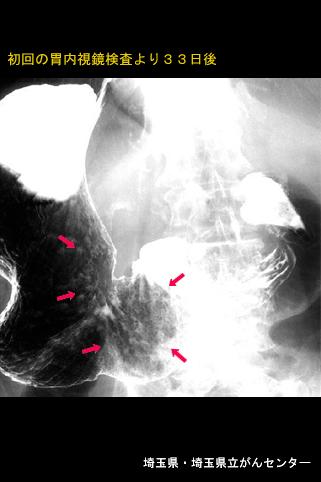

clasificación del pacienteTumor Epitelial Maligno/Adenocarcinoma

parte(separada por órganos)estómago(región)/mas de dos

método de exámenRayos X

clasificación ectoscópica de tumoresTipo 0(tipo superficial)/Tipo IIc(IIc+IIa)

diámetro mayor del tumor40 -

grado de penetraciónsm

múltiples tumores(en un mismo órgano)presente(simultáneo)